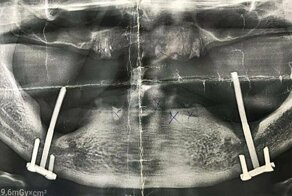

30-летний житель Лесосибирска просто стоял и ждал на остановке автобус, когда из-под колес ему в лицо прилетело нечто огромное и тяжелое. На рентгенографии врачи смогли визуализировать большой металлический болт, который раздробил несколько костей и повредил дно правой глазницы.

Ожидая общественный транспорт, никогда не знаешь, чем может закончиться твой день. Антон Б, житель Красноярского края, просто стоял на обочине, когда из-под колес проходившего рядом грузовика вылетел какой-то предмет, ударивший его в лицо. С челюстно-лицевыми травмами мужчина был доставлен в Лесосибирскую ЦРБ. Томография показала крупный болт с гайкой размером 6,2х2,5 см, который визуализировали под раздробленной правой скуловой костью.

МСКТ до операции

Как видно на рентгенографическом снимке, болт повредил несколько костей черепа и задел дно глазницы.